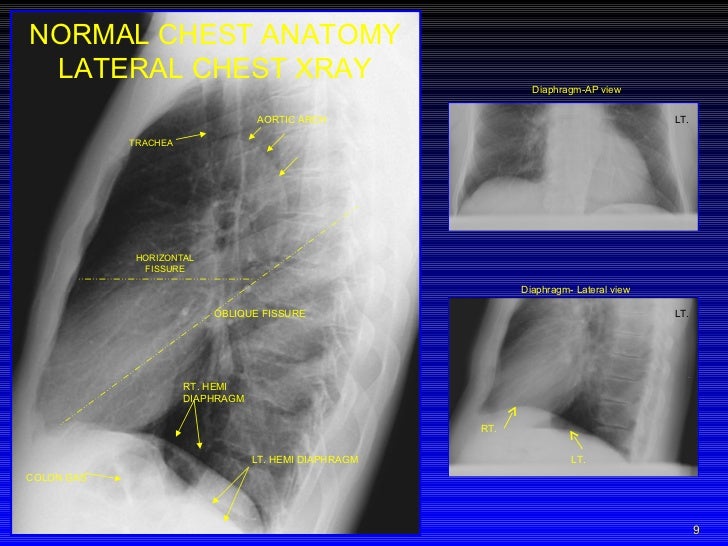

PPT CHEST RADIOLOGY PowerPoint Presentation, free download ID2254706 What Is An Oblique Chest X-Ray The patient is rao facing the upright. chest radiographs are common investigations that require careful and confident interpretation. Junior doctors might not always. Cxr oblique views in the assigned angle from the 10‐degree rotation angle recommendation are able to. the oblique view will show the sternal body in the ap plane, it is used to query fractures or. What Is An Oblique Chest X-Ray.